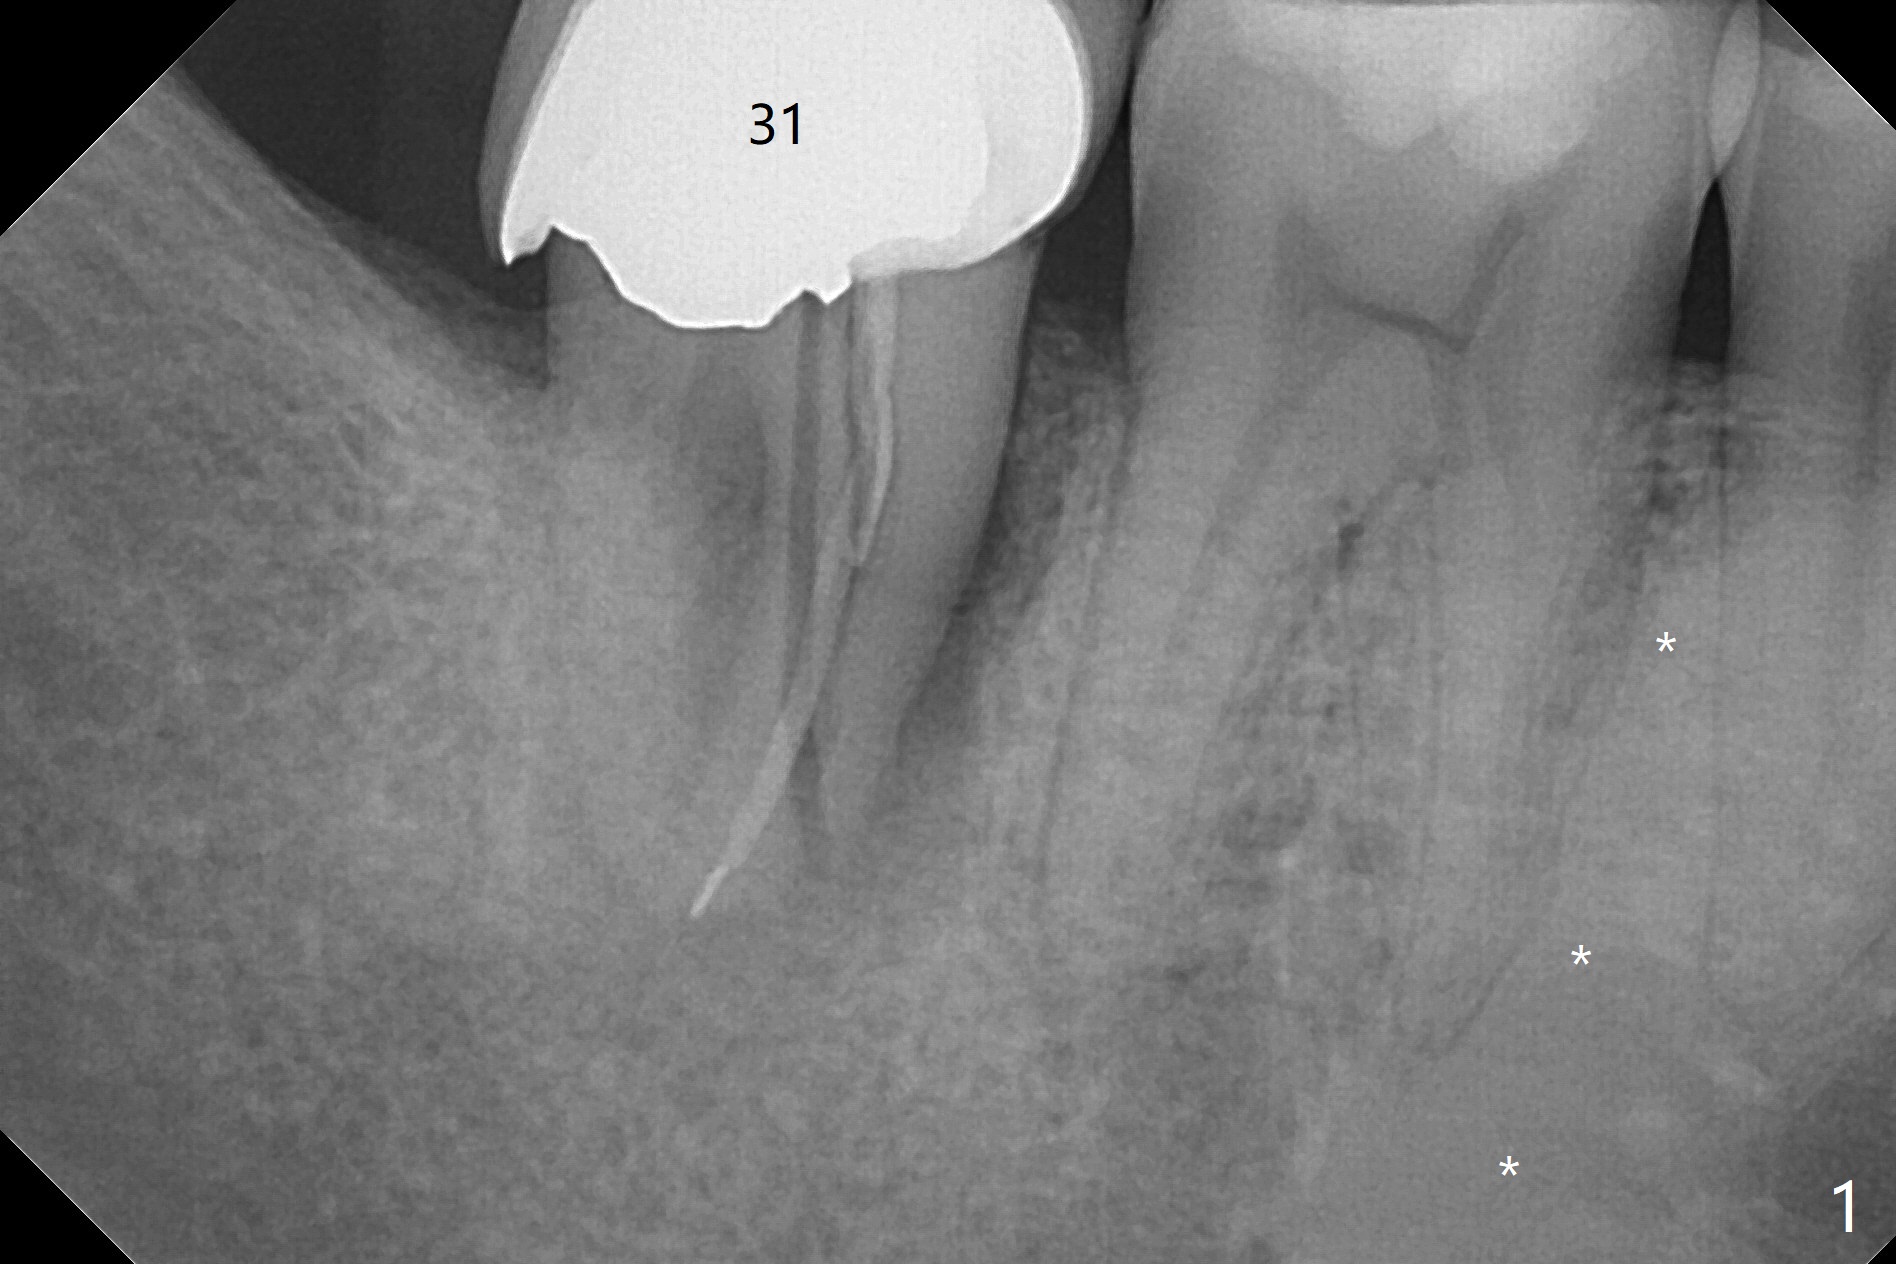

根裂

34岁男抱怨右下7根管治疗后牙齿松动,根尖片证实根裂(图一),第二前磨牙和第一磨牙之间有致密骨质(图一:*,图三)。尽管患牙周围骨质吸收严重,尤其是颊侧牙槽嵴(图二:B),必须做即刻种植。植骨有时效果不佳,没有减少手术难度。拖延治疗可能增加对合牙过度萌出,尤其是咬合力大病人。虽然植体颊侧螺纹有暴露危险(图四:>),但是颊侧牙龈附着很长(双箭头),结合基台(图五:粉红色)和临时牙冠(白色),牙龈创造有利的植骨床(红色:骨粉)。